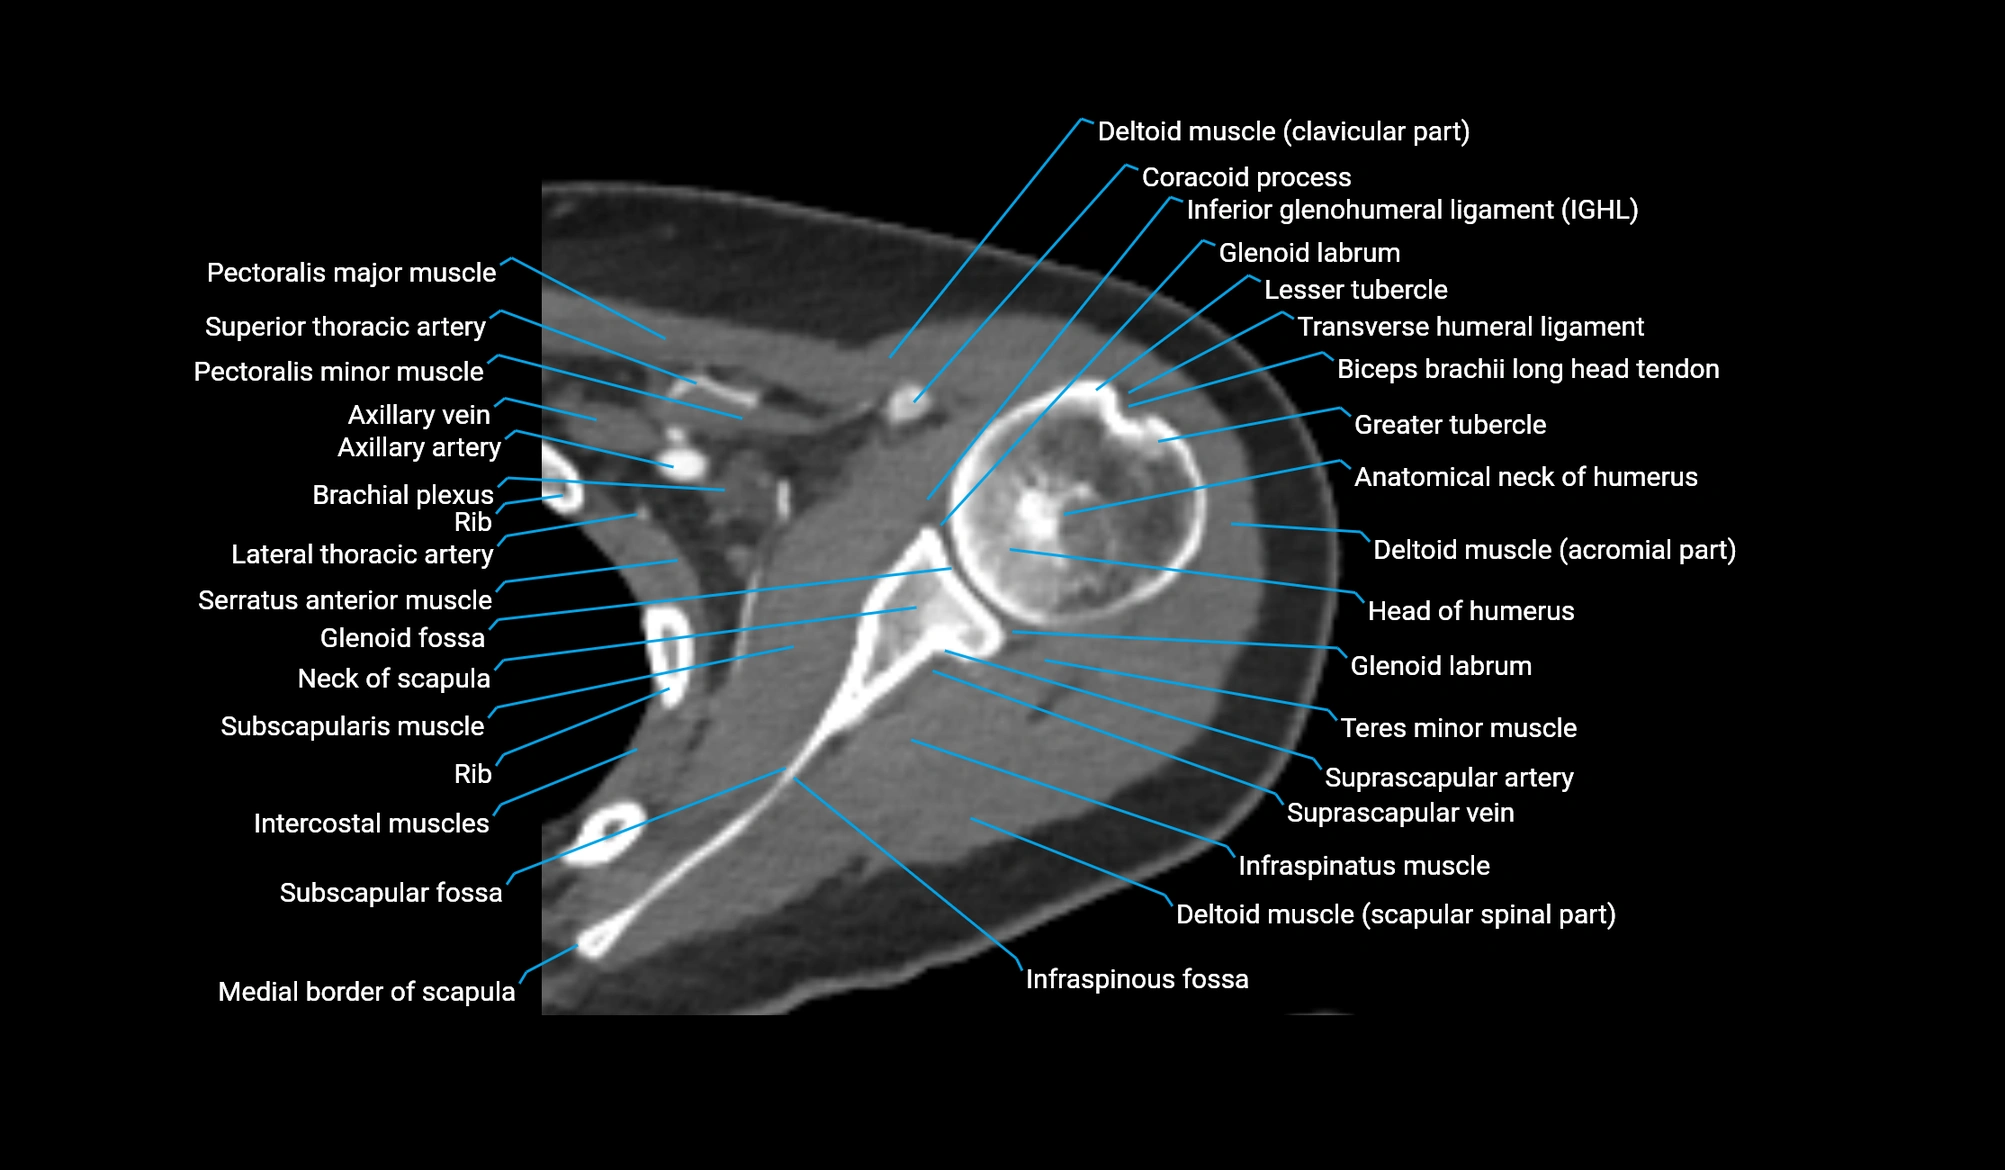

CT image